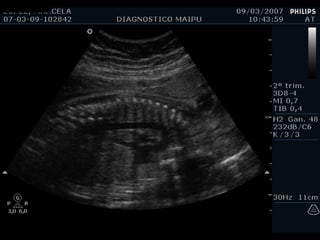

Cámaras COLUMNA AORTA ESTERNON VP VP BANDA MODERADORA FLAP VI VD AI AD

Tamaños

Tamaño